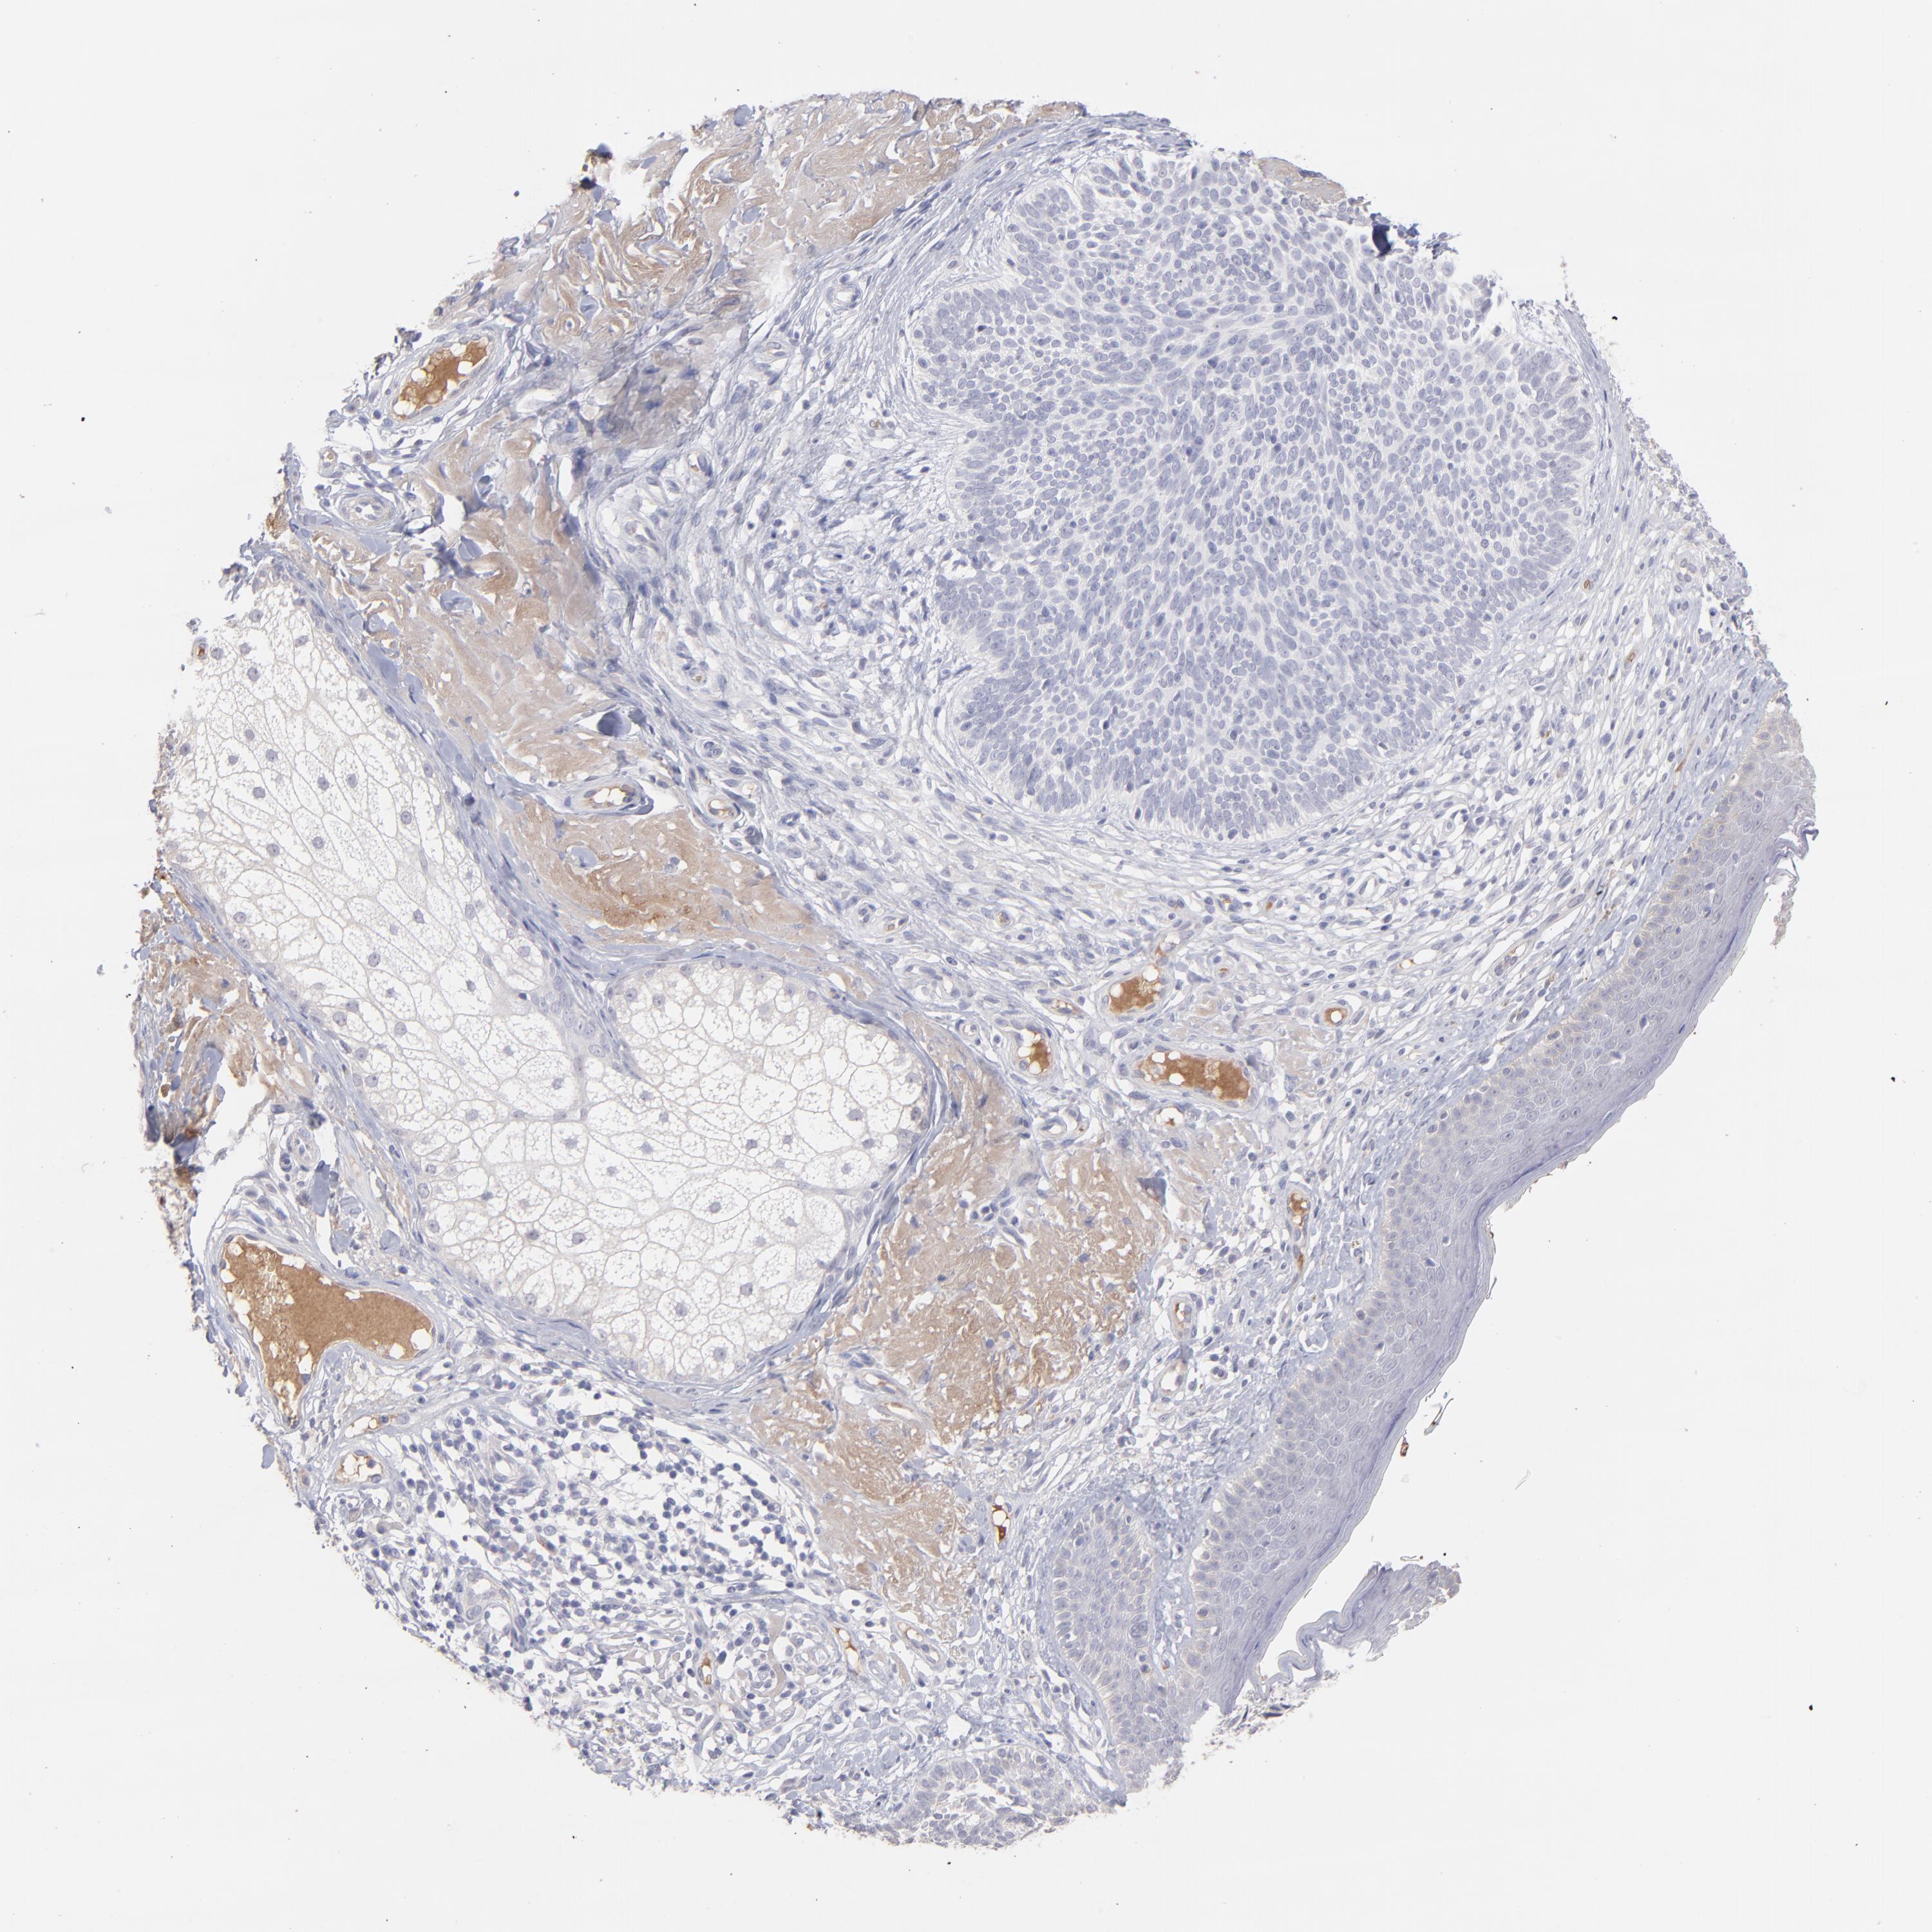

Basal cell and squamous cell cancer

SKIN CANCER - Protein expressioni

A mouse-over function shows sample information and annotation data. Click on an image to view it in a full screen mode. Samples can be filtered based on level of antibody staining by selecting one or several of the following categories: high, medium, low and not detected. The assay and annotation is described here.

Antibody stainingi

Antibody staining in the annotated cell types in the current human tissue is reported as not detected, low, medium, or high, based on conventional immunohistochemistry profiling in selected tissues. This score is based on the combination of the staining intensity and fraction of stained cells.

Each image is clickable and will lead to virtual microscopy that enables deeper exploration of all samples and also displays staining intensity scores, fraction scores and subcellular localization as well as patient and tissue information for each sample.

Antibody HPA003827

Antibody HPA052139

Staining

High

Medium

Low

Not detected

Intensity

Strong

Moderate

Weak

Negative

Quantity

>75%

75%-25%

<25%

None

Location

Nuclear

Cytoplasmic/membranous

Cytoplasmic/membranous,nuclear

Squamous cell carcinoma, NOS

Basal cell carcinoma